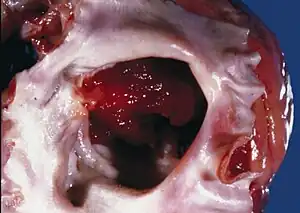

A cardiac myxoma is a noncancerous tumor of the heart that may embolise and grow at the site of embolisation.[1] Symptoms depend on the tumor size, location, shape, mobility and how fast it grows.[1] More than two-thirds have severe symptoms such as heart failure, stroke and embolisation.[3] Up to a fifth may have no symptoms.[1] Typical presentations include shortness of breath, feeling faint, chest pain, palpitations, fever, weight loss and joint pains.[1] There may be sudden death.[1]

Although any chamber may be affected, most arise within the left atrium near the valve of the fossa ovalis.[1] It may run in families as part of Carney syndrome, or may occur sporadically.[2] The tumor is derived from multipotent mesenchymal cells.[4]

Myxomata are the most common type of adult primary heart tumor.[4] [8] Most myxomata arise sporadically (90%), and only about 10% are thought to arise due to inheritance.[9]